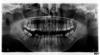

Lapav Опубликовано 17 июня, 2011 Поделиться Опубликовано 17 июня, 2011 Доброго времени суток!мне 30 лет, решил "подправить" расположение зубов.В четырех клиниках - предложили, естественно, 4 разных плана Принципиальный вопрос который меня беспокоит - можно ли обойтись без удаление четверок на ВЧ?Где-то прочитал, что из-за этого могут произойти изменения профиля лица, улыбки, "старение" и т.п....крайне нежелательный, возможный и непредсказуемый (как мне кажется) побочный эффект. мнения врачей по этому вопросу разделились 50/50 - два специалиста сказали, что можно исправить не удаляя, а со слов других - категорично требуется удалять зубы на ВЧ, без этого ничего не получится! Второй момент - утянут ли микроимплантами 7ки и 8ки на НЧ?..устанавливать импланты не хочу сам, вопрос не в деньгах, а в возможности лечения с наименьшим вмешательством. Временем для длительного лечения располагаю более чем! Ссылка на комментарий

Force Опубликовано 18 июня, 2011 Поделиться Опубликовано 18 июня, 2011 http://forum.stom.ru/index.php?showtopic=4655 вопросы требуют как минимум трг и фото!!! 1 Ссылка на комментарий